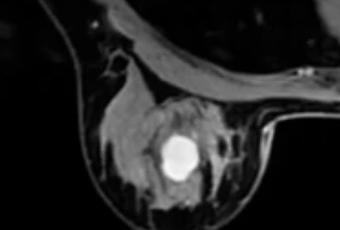

Caso de resonancia magnética de mama

lesion híper intensa en t1, con márgenes bilobulados, con bordes bien definidos, que tras contraste presenta un realce precoz intenso, con curva tipo 3 de lavado apartir del segundo minuto, el valor de ADC fue claramente superior de 1,60 x 10 mm/seg

cual es el diagnóstico??